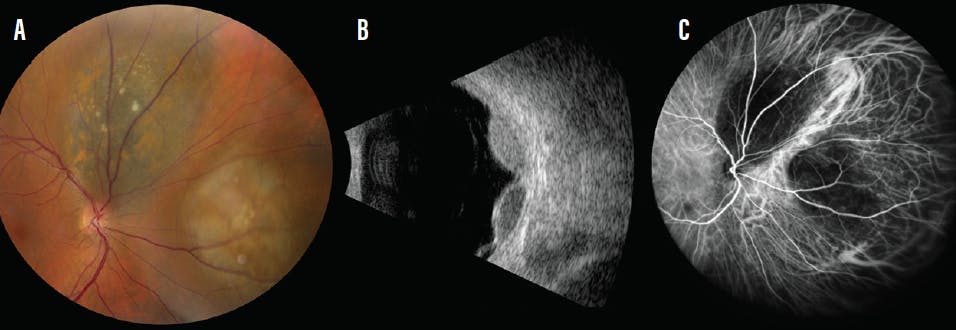

On our examination, VA was 20/25 OD and 20/20 in the left eye (OS). IOP was 13 mm Hg in each eye. On anterior segment examination, there was no ocular melanocytosis on either eye. However, two iris freckles were noted OS. Fundoscopic examination of the left eye was unremarkable. Funduscopic examination of the right eye showed two independent small choroidal melanomas located superonasal to the optic disc and nasal to the optic disc (Figure, A).

B-scan ultrasonography documented two distinct echolucent tumors, with No. 1 (superonasal) measuring 9.0 mm in base and 4.6 mm in thickness and No. 2 (nasal) measuring 9.0 mm in base and 4.3 mm in thickness (Figure, B). There was no extrascleral extension, and the two tumors were distinct.

Fluorescein angiography revealed patchy areas of hyperfluorescence in both tumors during the arteriovenous phase. Indocyanine green angiography displayed the tumors as hypocyanescent and with no evident connection between the two independent melanomas (Figure, C). Autofluorescence revealed prominent orange pigmentation over both tumors.

Figure. Multifocal choroidal melanoma in the right eye of a 56-year-old woman (A). B-scan ultrasonography showed two distinct hollow, dome-shaped lesions with subretinal fluid (B). Evaluation with indocyanine green angiography documented hypocyanescence at the two tumor sites with normal choroidal flow in between, implying two distinct tumors (C).